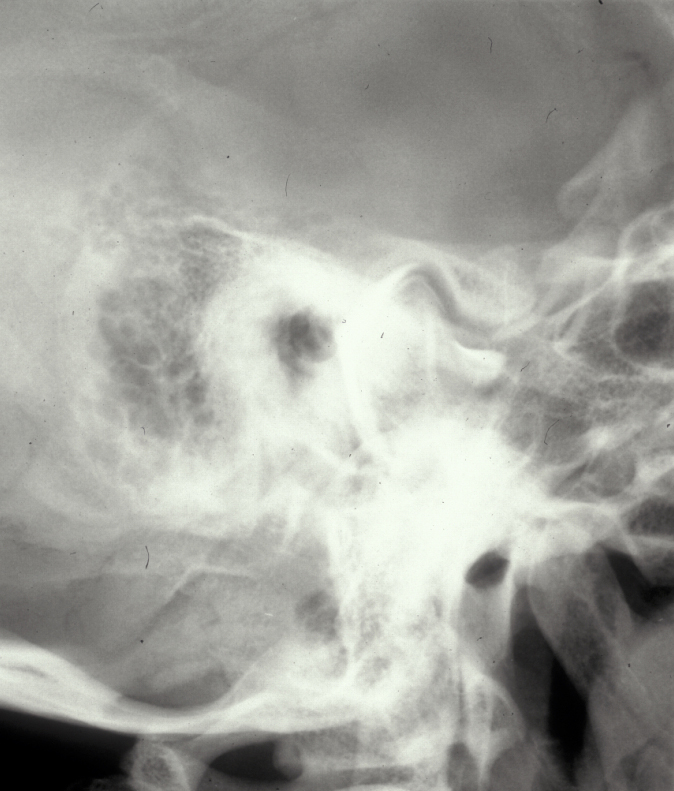

TMJ arthrography involves the direct injection of a contrast medium into one or both of the joint spaces and provides information on joint function, particularly that of the meniscus. TMJ arthrography is a technically demanding investigation (see Figure 6).

Figure 6: Lower joint space arthrogram of the temporomandibular joint; technically more demanding than plain X-ray radiographs but more readily interpreted.